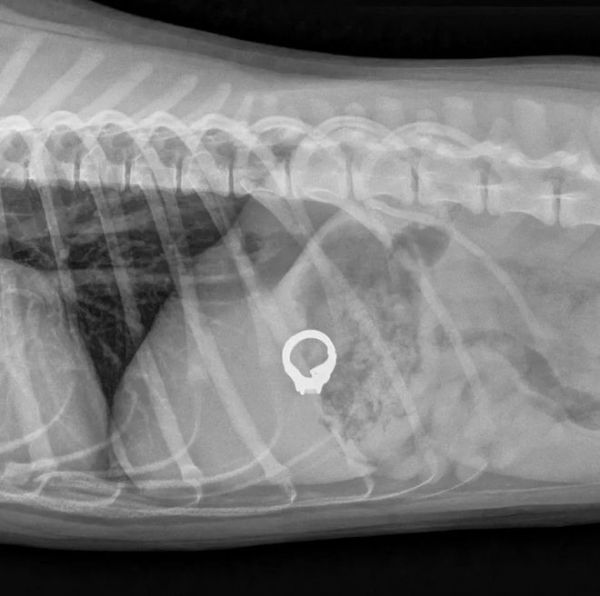

“在狗狗肚子里找到了丢失的结婚戒指”

有这样一位心大的铲屎官,不小心居然把珍贵的结婚戒指弄丢了。满屋子找结婚戒指,一无所获。最后不得不动用金属探测仪来找那枚丢失的戒指。

房间里的每个角落都仔仔细细地探测了一遍,还是没有任何发现。有时候就是那么无奈,在铲屎官准备放弃的时候,家里的一只狗狗靠近探测仪,居然发出了警报。

戒指被狗狗吃了?铲屎官下意识闪过这样的念头。到医院检查后发现,戒指竟然真的在狗狗肚子里。

一番折腾,铲屎官总算拿回了戒指,狗狗也为这次吞食异物受了不少罪。